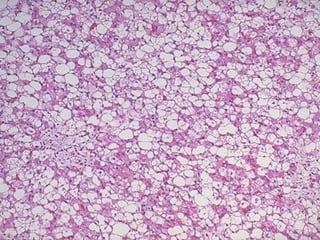

• Histologically : Mature fatty tissue

NORMAL FAT LIPOMA,

encapsulated